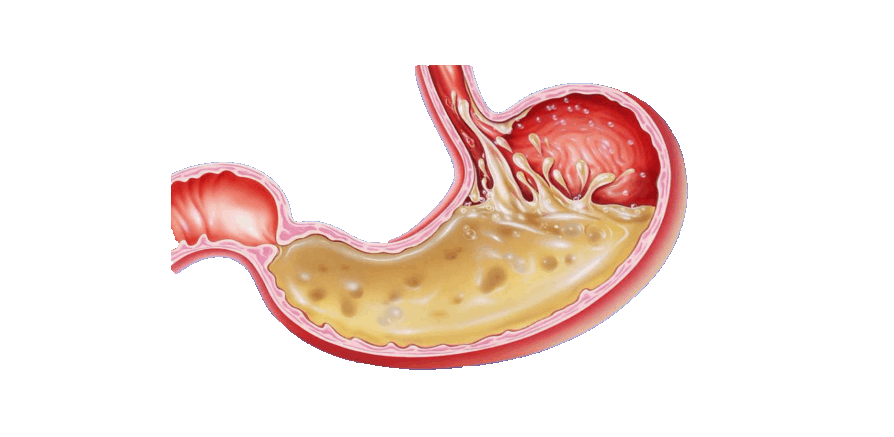

Информация и фотографии о хроническом гастрите и дуодените